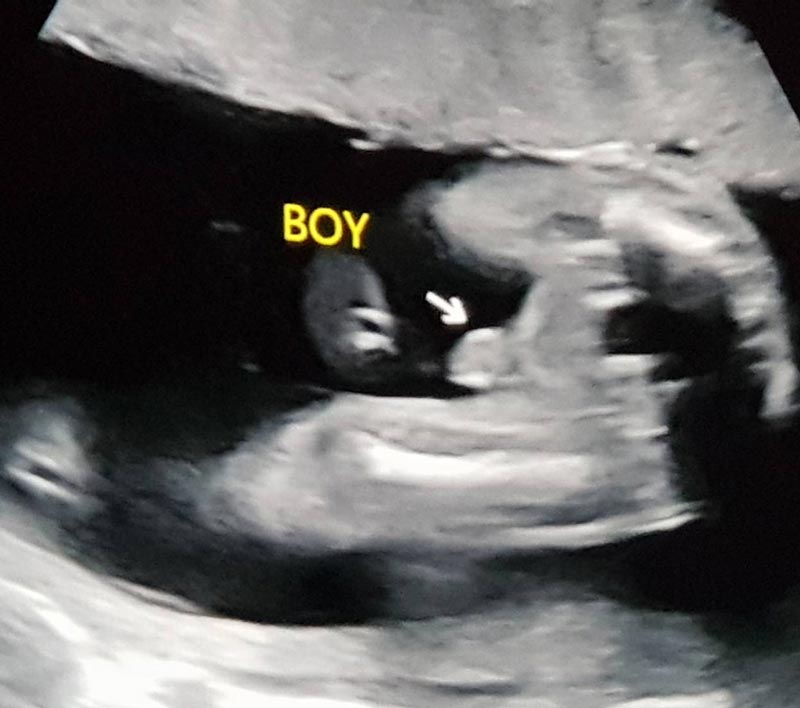

"ในที่สุดลูกชายแม่ก็มา ขอบคุณสวรรค์ที่มอบลาภอันประเสริฐมาให้ ดีใจที่สุดเลย #ฟินเวอร์ #น้ำตาคลอ แม่ซึ้งเห็นผู้ชายแล้วน้ำตาไหล ... เป็นเรื่องราวดี ๆ ที่เข้ามาอีกเรื่องในชีวิต ขอบคุณทุกๆคำอวยพรจากทุกๆคนนะคะ แม่ฟินมากกกกกกกพูดเลยยยย #20weekspregnant #welcomemyboy สามีพี่ยิ้มกว้างมากกกกก @por_tnp"